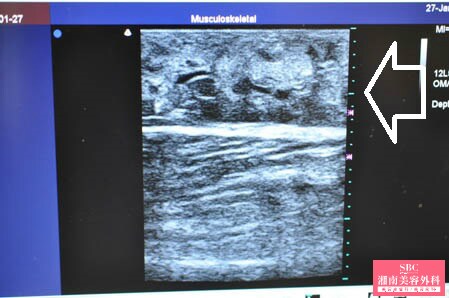

No.169070【脂肪吸引】湘南美容外科・全ドクターの脂肪吸引最高責任者であるあの有名な根こそぎ竹田先生の劇的ビフォーアフター!〜術中動画あり!筋肉質なふくらはぎを徹底的に根こそぐ!術中3Dタッチビュー・右ふくらはぎ〜

画像上しっかりと皮下脂肪は根こそがれており

間違いなく患者様のご期待にはそえられると思います。